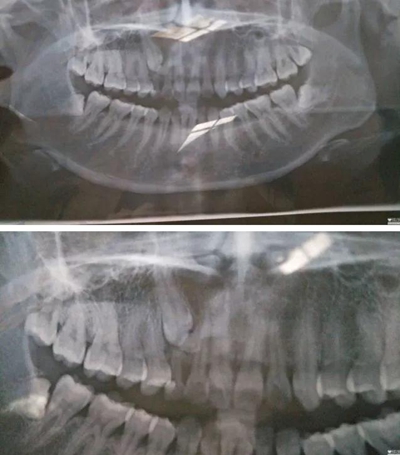

2017年6月18日,牙疼…之前補(bǔ)過(guò)一次,這次估計(jì)是發(fā)炎了,然后被伊森告知乳牙滯留,恒牙阻生,要拍片確認(rèn)恒牙是否完好,才能進(jìn)行下一步…鎮(zhèn)醫(yī)院,設(shè)備不齊全,伊森建議去大醫(yī)院拍片…

心里著急,第二天就跑到廣東省口腔醫(yī)院花了一天的時(shí)間排隊(duì)拍片,然后被伊森建議去矯正科詳細(xì)咨詢(xún)…然后矯正伊森就跟我說(shuō)了大概治療方案,時(shí)間和費(fèi)用,先拔掉四顆智慧牙,然后帶牙套矯正牙齒,期間會(huì)拔掉小虎牙給埋伏牙做牽引(我情況比較復(fù)雜,下面有兩顆埋伏牙,還得拔掉其中一顆)╭(°A°`)╮而且還不一定牽引成功,如果不成功,最后矯正后期還要種植牙齒(?_?)…要花3-4W,長(zhǎng)達(dá)2年時(shí)間…當(dāng)時(shí)就震驚了,從沒(méi)想過(guò)自己這口牙辣么貴,辣么麻煩…

跟LG一起確定了矯正之后,立馬打電話(huà)給伊森預(yù)約了7.3號(hào),然后LG陪我一起去了醫(yī)院,伊森詳細(xì)了解了婚姻狀況,生娃狀況(對(duì)于我已經(jīng)有兩個(gè)娃的事實(shí)表示了各種驚訝),然后拍片,倒模具,定制方案,約定下次就診時(shí)間…

然后被伊森告知了一個(gè)不好的消息,(?_?)我乳牙下面的牙經(jīng)集體開(kāi)會(huì)討論一直認(rèn)為牽引不上來(lái),需要矯正完成后去種植,費(fèi)用要1-1.5W,瞬間心都涼了T^T,期間繼續(xù)不死心的重復(fù)問(wèn)可不可以牽引,估計(jì)所有人都會(huì)覺(jué)得牙齒還是原配的好…結(jié)果還是令我失望〒_〒